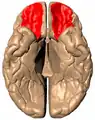

Orbital gyrus shown in red

Basal surface of cerebrum. Orbital gyrus shown in red.